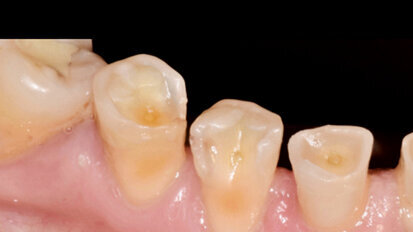

Nový úsměv za jeden den

Čt. 28. května 2020